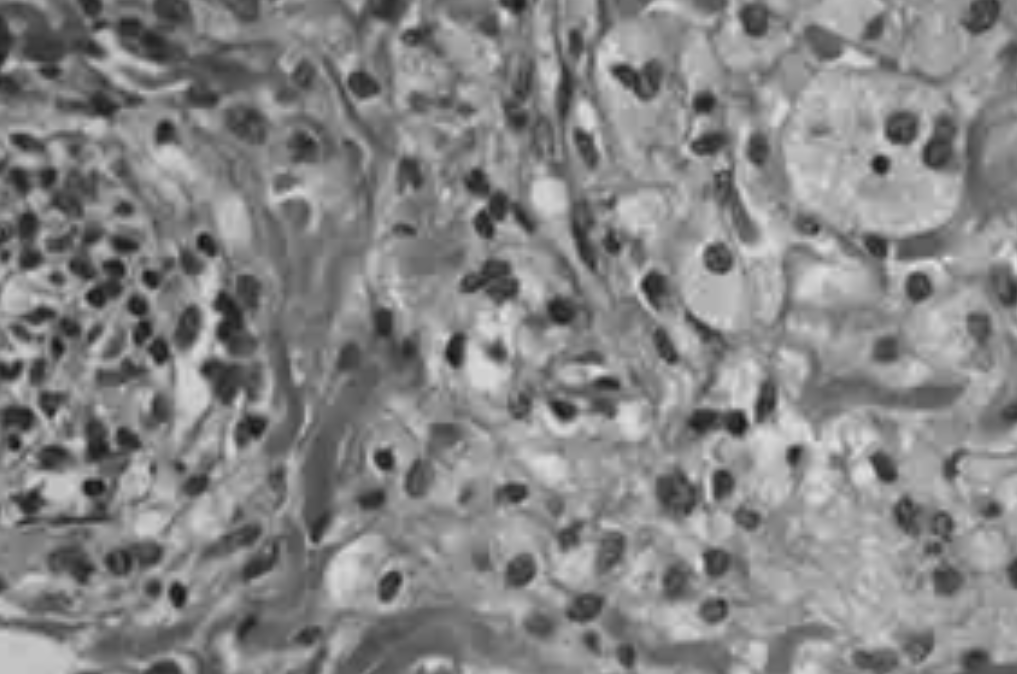

Esta patología es considerada una histiocitosis rara con menos de 2.000 casos registrados en todo el mundo y que es potencialmente mortal. Las histiocitosis se caracterizan por una proliferación descontrolada de células sanguíneas, que migran a diferentes órganos, donde provocan una inflamación y el consiguiente daño.